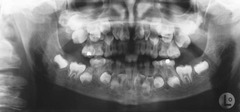

-obstruction in the gland hard nodule in soft tissue at a salivary gland -calcification of material -can be seen radiographically

Back